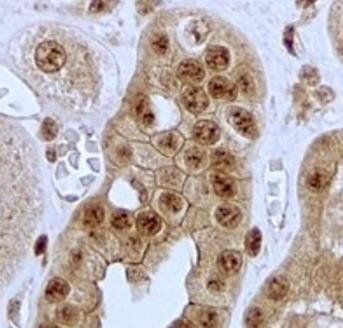

| Application notes | IHC: In paraffin embedded Human Kidney shows membrane staining in the epithelial cells of convoluted tubules. Recommended concentration, 2-4 μg/ml. |

Immunohistochemical staining of Human Kidney using JAG1 antibody